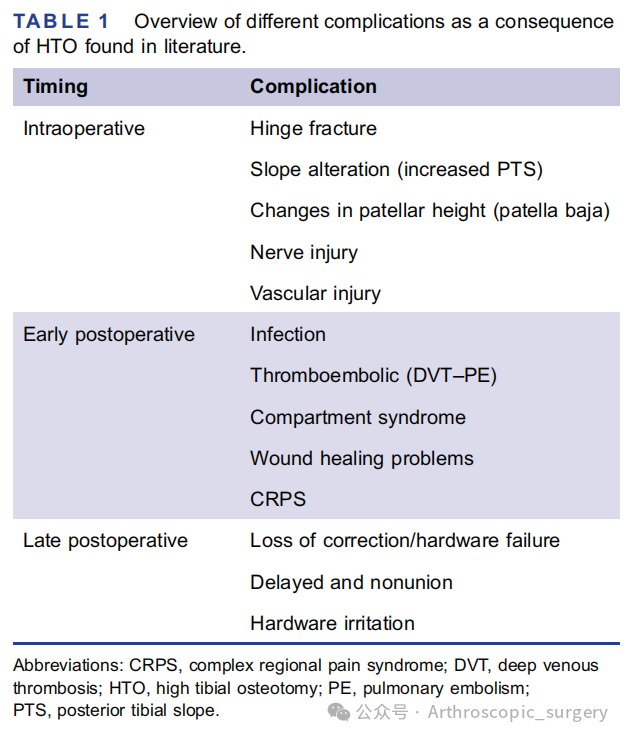

HTO术中及术后各类并发症列表